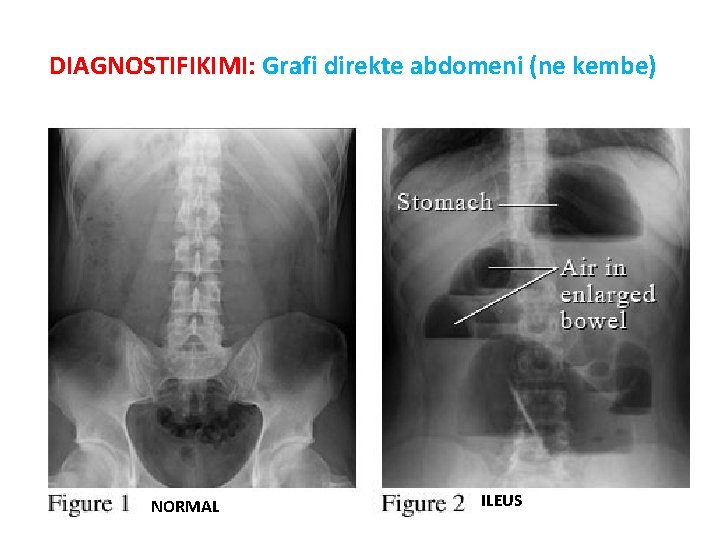

DIAGNOSTIFIKIMI: Grafi direkte abdomeni (ne kembe) NORMAL ILEUS